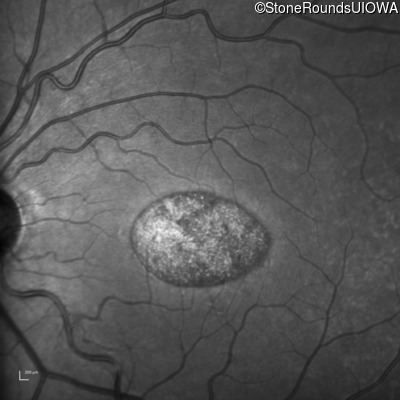

This 22 year old man had macular abnormalities noted incidentally at a routine eye exam at age 19. Since then, he has experienced a gradual loss of acuity particularly in the left eye.

| AR Stargardt Disease | ABCA4 | Tyr245Stop TAT>TAG | Unknown | AR |